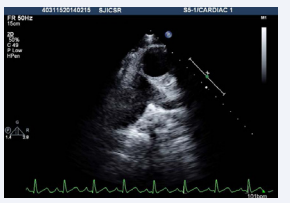

A 22-year-old male was referred to our tertiary care institute with a diagnosis of double outlet right ventricle with a ventricular septal defect and malposed great arteries. The patient was evaluated in the referring institute for atypical chest pain for ten days without any significant past history. A clinical examination, including cardiac testing, was normal, and the resting oxygen saturation was 98% on room air. Although the transthoracic echocardiographic window was poor, it revealed the patient had situs solitus, and there was AV and VA concordance. The aorta was located to the left and anterior to the pulmonary artery (Figures 1,2, video 1,2)

Figure 2: Transthoracic echocardiogram basal short axis view showing aorta to the left and anterior of pulmonary artery